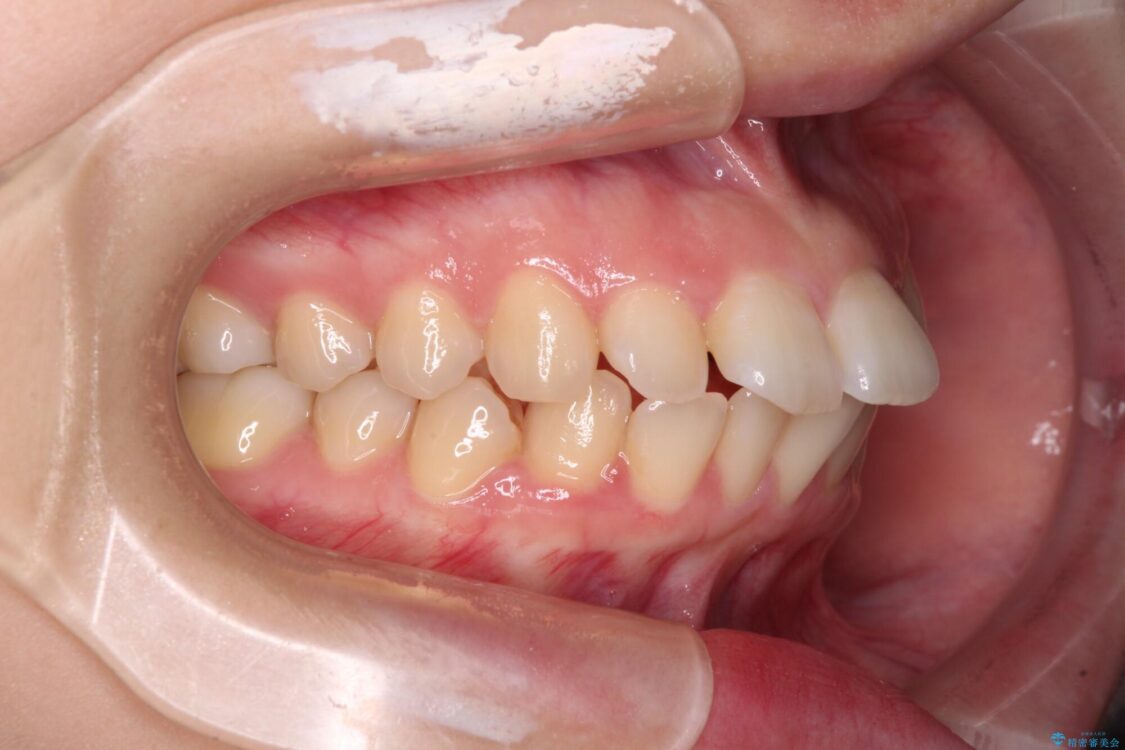

上下の前歯が突出しており、口が閉じにくいとのことで来院された患者様です。

上下前歯が著しく前突している状態であったので、上下左右の第1小臼歯4本を抜歯し、ワイヤー装置にて矯正治療を行うこととしました。

治療前